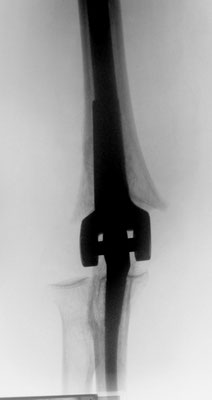

Ellenbogennaher Oberarmbruch/suprakondyläre Oberarmfraktur

Diese Brüche gehen häufig mit einer erheblichen Zertrümmerung des Knochens einher. In den meisten Fällen ist auch die Gelenkfläche betroffen, so dass eine operative Rekonstruktion erforderlich ist. Wie bei allen gelenknahen Knochenbrüchen besteht die Aufgabe darin, ein sehr kurzes Knochenfragment an dem Schaftknochen zu befestigen und die Gelenkfläche stufenlos wieder herzustellen. In der Standardtechnik werden dabei zwei Platten benutzt. Dabei geben insbesondere die winkelstabilen Titanplatten optimale Möglichkeiten um die kleinen Knochenteile stabil zu befestigen.

Ist allerdings die Gelenkfläche so stark zerstört, dass eine Rekonstruktion nicht möglich ist, bietet sich bei Patienten in höherem Lebensalter die Implantation einer Ellenbogenprothese an. Mit dieser ist eine gute Funktion zu erreichen.